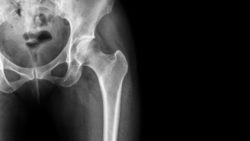

Stryker hip replacement lawsuit filed on complicationsAfter adverse side effects and complications allegedly developed following the implantation of the Stryker LFIT V40 Femoral Head, a man filed a Stryker hip replacement lawsuit against the manufacturers, Howmedica Osteonics Corp.

According to the short form complaint, plaintiff Jude G., a resident of the state of Louisiana, states that he was implanted with the Stryker hip device on Oct. 1, 2009, at Our Lady of the Lake Regional Medical Center. He was also implanted with the Accolade TMZF during the hip replacement procedure.

Following reports of severe adverse side effects and complications pertaining to the LFIT Anatomic V40 Femoral Head, a voluntary recall was announced by Stryker Orthopedics on Aug. 29, 2016. It was released as an “Urgent Medical Device Recall Notification.” The notice of the recall was released to surgeons and medical offices across the country that were utilizing the hip replacement device.